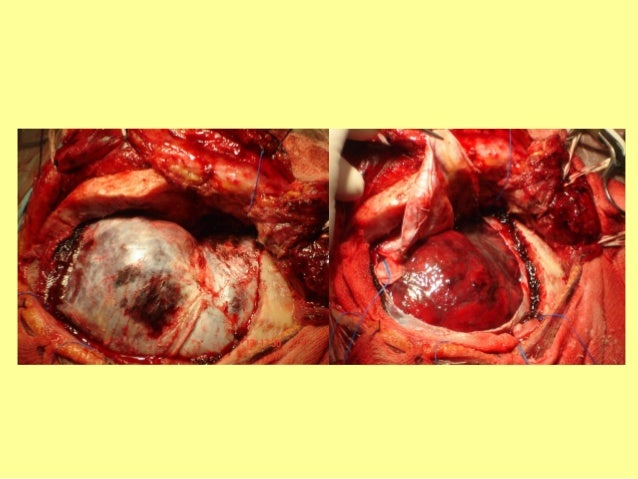

25. 25. HEMATOMA SUBDURAL AGUDOHEMATOMA SUBDURAL AGUDO

27. 27. HEMATOMA SUBDURAL AGUDOHEMATOMA SUBDURAL AGUDOHSA POSTRAUMÁTICAHSA POSTRAUMÁTICACONTUSIÓN HEMORRÁGICACONTUSIÓN HEMORRÁGICA